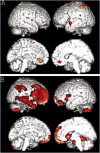

Figures